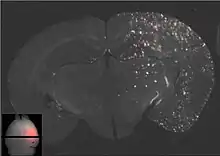

Les ultrasons peuvent être focalisés sur n'importe quel domaine du cerveau. C'est ainsi que l'on peut ouvrir la barrière hémato-encéphalique sélectivement sur des régions délimitées du cerveau. Les médicaments administrés pénétreront alors sur la zone ainsi ciblée[138]. On peut suivre le ciblage des zones par une IRM simultanée : il suffit d'administrer un produit de contraste IRM, comme du gadolinium convenablement chélaté, qui pénètre dans le cerveau à travers les parties de la barrière hémato-encéphalique ouvertes. Ces parties deviennent alors visibles en IRM. Les produits de contraste ne sont pas en mesure de franchir la barrière aux endroits où elle n'est pas ouverte.

Le mécanisme de l'ouverture de la barrière hémato-encéphalique par utilisation d'ultrasons focalisés et de microbulles n'est pas encore complètement élucidé. L'interaction entre les ultrasons et les microbulles y joue un grand rôle, et conduit in vivo à toute une série d'effets biologiques[143]. Il semble qu'un grand rôle est joué par les forces de cisaillement créées par les microcourants. Ces microcourants eux-mêmes proviennent des oscillations des microbulles dans le champ d'ultrasons[143]. On sait déjà que les endothéliums peuvent réagir dynamiquement aux forces de cisaillement, et que ces forces de cisaillement sont une grandeur critique pour l'homéostasie[144]. Les vues en microscopie électronique des capillaires d'animaux ainsi traités présentent des signes aussi bien de transport transcellulaire que paracellulaire de molécules marqueurs (péroxydase du raifort). Le transport transcellulaire est la transcytose, tandis que le transport paracellulaire est initié par un processus complexe de désintégration, qui fait perdre leur fonction aux jonctions serrées[145].

La barrière hémato-encéphalique ainsi ouverte est perméable pour les médicaments de chimiothérapie de faible masse moléculaire, comme la doxorubicine[146], et des anticorps come le Trastuzumab[147],[148],[149]. La faisabilité de principe du transport dans le cerveau a été démontrée avec cette méthode même pour des gènes sur des modèles animaux[150],[142]. Le procédé d'ouverture de la barrière hémato-encéphalique par ultrasons et injection simultanée de microbulles en est encore à ses débuts. Jusqu'à présent, il n'a été testé que sur des animaux. L'expérience conduit à penser qu'il se passera encore de nombreuses années jusqu’à ce qu'il soit autorisé sur l’homme.